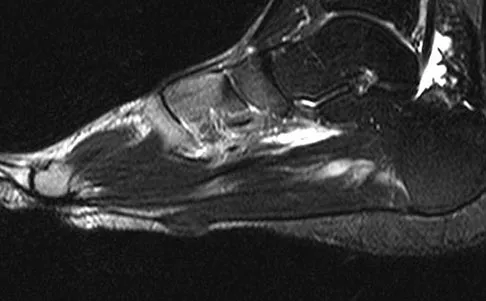

A 45-year-old man who underwent an ankle arthrodesis reports that for the first 6 years he had significant pain relief after the fusion healed. However, he now has increasing pain in the sinus tarsi. AP and lateral radiographs are shown in Figures 8a and 8b. What is the most likely cause of the patient's symptoms?

The patient has a solid ankle fusion radiographically. With a tibiotalar arthrodesis, the adjacent joints (subtalar and transverse tarsal) take additional stress. Over time, progressive degenerative arthritis will occur in these adjacent joints, often necessitating further surgery. Beaty JH (ed): Orthopaedic Knowledge Update 6. Rosemont, IL, American Academy of Orthopaedic Surgeons, 1999, pp 613-631.